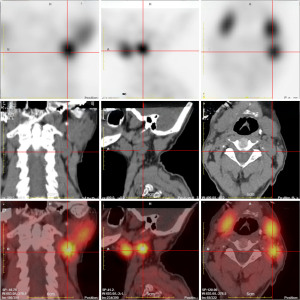

Further localization of the suspected ectopic parathyroid lesion was performed using single-photon emission computed tomography/computed tomography (SPECT/CT) with 99mTc-sestamibi parathyroid scintigraphy. No definitive uptake was noted in the typical anterior parathyroid regions. However, an ovoid, slightly hyperdense lesion was identified in the left cervical level II–III region, exhibiting patchy areas of lower density. These imaging features were highly suggestive of an ectopic parathyroid adenoma (Figure 5). Although not available in our institution at that time, 18F-fluorocholine positron emission tomography (PET)/CT has been increasingly recognized as a highly sensitive imaging modality in patients with ectopic or inconclusive parathyroid adenomas.